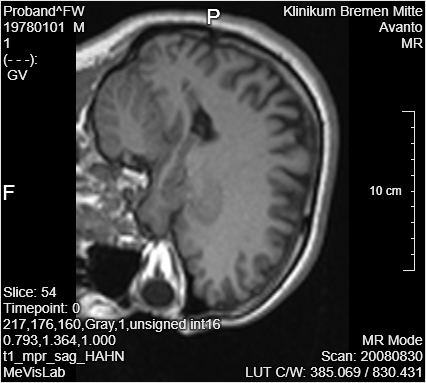

The coordinates in PyTorch are also a little bit different than in MeVisLab; therefore, you have to rotate the image. Add an OrthoSwapFlip module and connect it to the Resample3D module. Change

You can use the Output Inspector to see the changes on the images after applying the resample and a swap or flip.